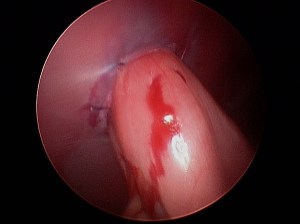

For the best possible outcome do not delay treatment! At this time, the gold standard approach is arthroscopic debridement (removal) of the fragmented cartilage and the surrounding diseased cartilage and subchondral bone. Curettage may allow the now vacant cartilage bed to fill in more quickly with what is called fibrocartilage. I likened the removal of the fragment to old wallpaper removal (very much oversimplified). Once the old wallpaper bubbles and tears, you need to remove all the damaged wallpaper in the periphery or else the wallpaper will continue to peel.

There are older techniques of opening the joint to get access to the cartilage flap, however the recovery time on this type of procedure is significantly longer than with arthroscopy. Also, potential complications are increased with an “open” technique than with arthroscopic techniques. Arthroscopy is a minimally invasive tool that allows us to both diagnose and treat this condition. Generally speaking the patient can walk on the surgery leg (even if both legs have surgery at the same time!) following an arthroscopic procedure. Generally 2-3 small ports are placed over the shoulder (2-4mm in length) and this allows us access to the joint and work within the joint.